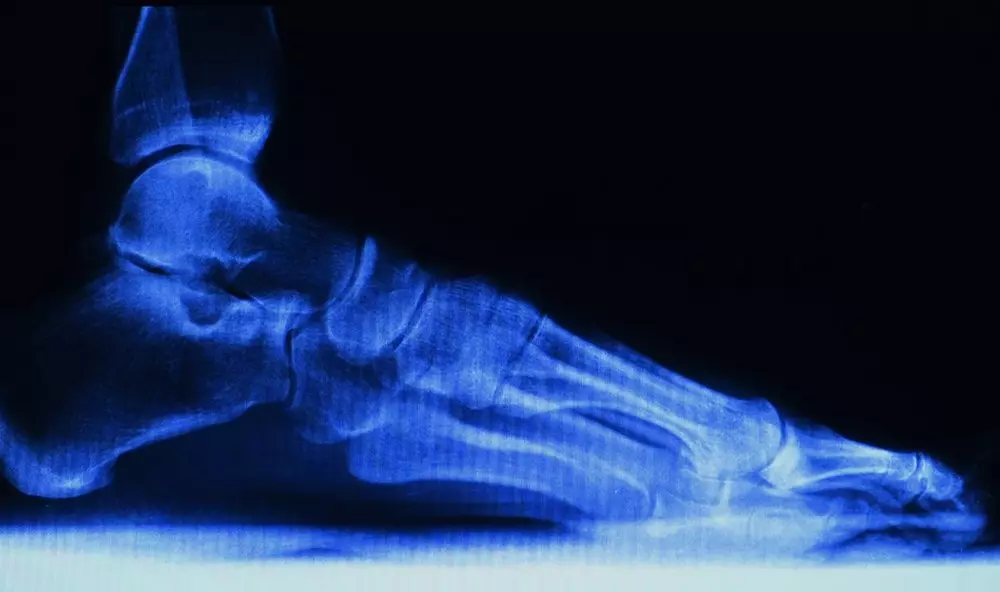

Temat numeru setnego wydania „Praktycznej Fizjoterapii i Rehabilitacji” brzmi „Diagnostyka różnicowa stawu skokowego i stopy – część 2.” Rozpoznanie urazu lub dysfunkcji w obrębie stopy i stawu skokowego to podstawa do podjęcia leczenia i wyboru odpowiedniego programu rehabilitacji. Błędna diagnoza jedynie nasili objawy lub doprowadzi do leczenia operacyjnego.

Diagnostyka różnicowa stawu skokowego i stopy

Piotr Godek wskazuje, że dysfunkcje stóp oraz stawu skokowego powstają jako konsekwencja urazu lub mikrourazów, a w wielu przypadkach jako następstwo zaburzeń osi biomechanicznej kości dolnej. Towarzyszy im ból lokalny, utykanie, ograniczenie zakresu ruchu lecz bez zauważalnych zmian wizualnych, czy w badaniach obrazowych. Zachęcamy do zapoznania się z diagnostyką różnicową różnorodnych wad, szeroko opisanych w najnowszym numerze.